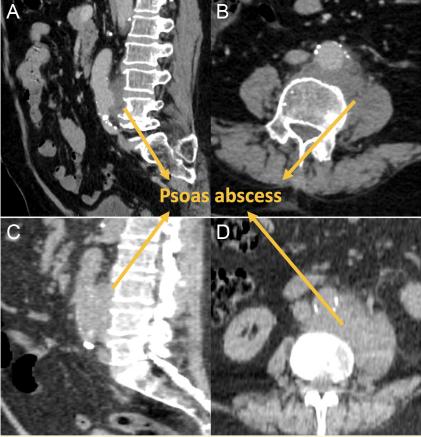

患者男性,75岁,因腰部疼痛放射到左下肢,伴发热和乏力被送进急诊室。既往史包括高血压和冠状动脉疾病外,余无明显病史。然而,患者最近的病史和就诊记录显示,他曾在1个月前因背部疼痛和发烧入住另一家医院。腹部CT发现腰肌脓肿,并开始静脉注射抗生素治疗(图1A和B)。建议脓肿引流,但患者不接受建议,出院后口服抗生素治疗。一个月后,患者以同样的主诉入院。入院时腹部CT扫描显示腰肌脓肿毗邻主动脉和左侧椎旁间隙(图1C和D)。

图1所示。(A-B)一个月前,腹部CT显示腹主动脉旁椎旁腰肌脓肿的轴位和矢状面图像。

(C-D)腹部CT示靠近腹主动脉椎旁区腰肌脓肿